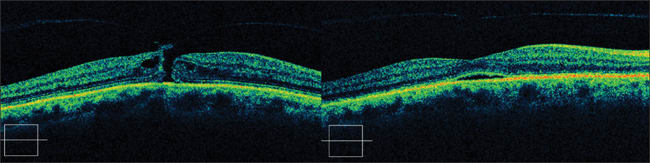

The initial clinical study, known as the Microplasmin Vitrectomy Study (MIVI I), was carried out on 60 patients with vitreomacular traction scheduled for surgery. Patients were divided into 6 groups of 10 patients each. Two phases were defined: one with a fixed dose (25 μg) but with time escalation (2 hrs, 24 hrs, 7 days), and the other with a fixed 24-hour exposure but ascending dose (25, 50, 75, 125 μg).26 Both safety and preliminary efficacy data were obtained. One patient developed a retinal detachment after receiving a dose of 25μg, with the initial symptoms starting 2 hours after administration. He ultimately developed a giant tear and required silicone oil for repair. Eleven percent of patients developed small peripheral tears as a PVD was surgically induced. This figure, while high, is in keeping with published series for noncannulated surgeries. No other safety issue was raised. Early efficacy data suggested that a prolonged exposure to microplasmin or increasing the dose was more likely to lead to a spontaneous PVD. Other studies have since been initiated and are confirming and extending these findings. Spontaneous closure of macular holes have been reported in the context of several trials (MIVI I, II, III) (Figure 2). In MIVI III, a United States–based study, 30% of patients had a spontaneous release of traction and did not require surgery (World Congress of Ophthalmology, 2008). These results suggest that pharmacologic vitreolysis may allow for nonsurgical treatment of macular traction syndromes. Other conditions resulting from an anomalous PVD may also benefit. One or more injections of microplasmin may be required to reach this goal. This will be the subject of future research.

Figure 2. Resolution of vitreomacular traction with the use of microplasmin 125 μg.